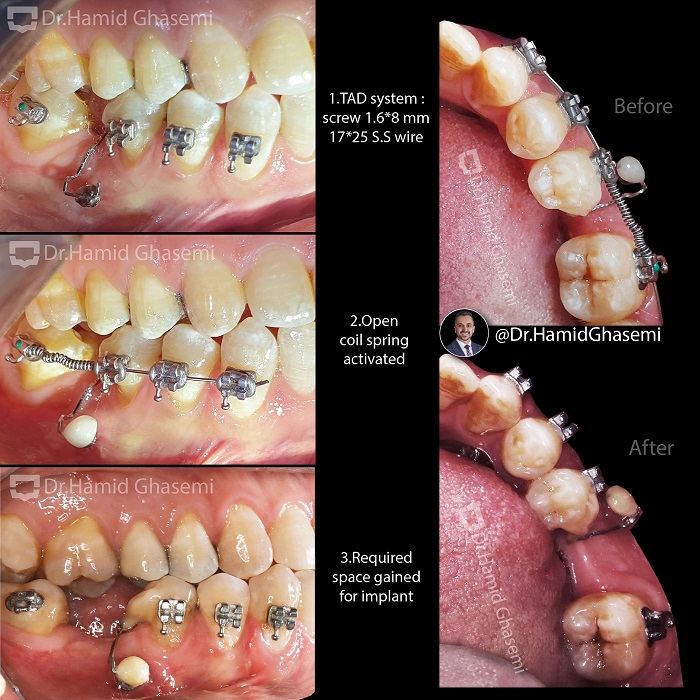

ارتودنسی دندان نهفته؛ راهحلی برای درمان مشکلات پنهان دندانها10 آذر 1403 - 6:20 ب.ظ